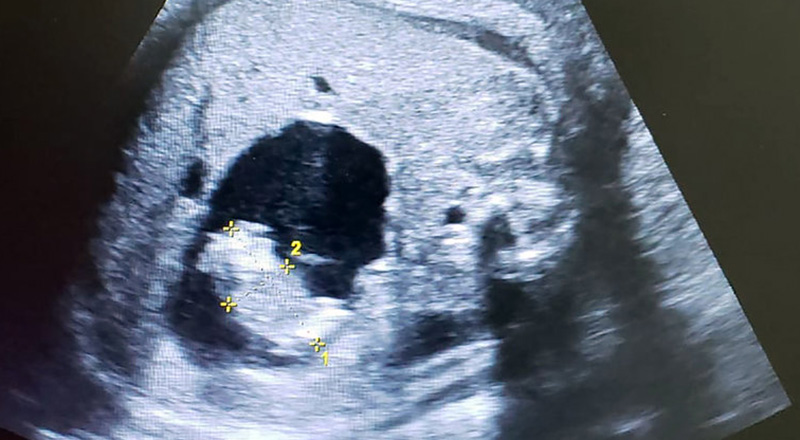

ROMA – Il feto di Itzamara cresceva nella placenta della sua mamma, ma intanto dentro di lei cresceva un altro feto: quello della sua gemella parassita. Questo il caso della bimba fatta nascere in Colombia ad appena 37 settimane dal dottor Miguel Parra-Saavedra, per essere operata e rimuovere il feto della sorellina che cresceva dentro di lei e altrimenti l’avrebbe uccisa.

La storia di Itzamara rappresenta un caso raro, ma non unico, in medicina. Si tratta del “fetus in fetu”, quando cioè all’interno del feto si sviluppa un altro feto, quello che sarebbe stato della sorella o fratello del futuro neonato.

Nel caso della bimba fatta nascere lo scorso 22 febbraio, la gemella parassita aveva il cordone ombelicale collegato con l’intestino della neonata. Un feto dotato di mani e piedi, ma privo di cuore e cervello, che continuava a crescere nella sua gemella rischiando di ucciderla. Per questo motivo il professore Parra-Saavedra, noto ginecologo consultato anche durante l’epidemia di virus Zika nel 2016 in Colombia, ha deciso di far nascere Itzamara prematura, una volta arrivata al peso di 3 chili.

Subito dopo la nascita, la piccola è stata operata perché la presenza della gemella parassita avrebbe potuto provocarle danni agli organi interni. Il feto infatti era lungo circa 5 centimetri e ora sarà sottoposto ad ulteriori analisi e test del Dna. Mentre in questo caso la presenza della gemella parassita ha messo a rischio la vita di mamma e neonato, spesso il “fetus in fetu” viene scambiato per una semplice cisti oppure per un teratoma, un tumore dei tessuti embrionali.